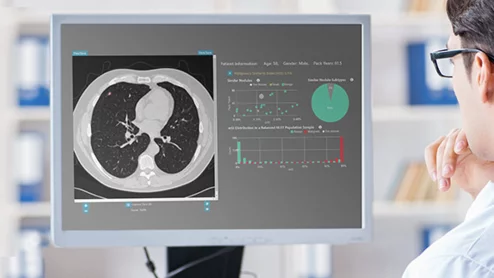

Unlike most AI tools that were built for specific applications like identifying stroke, the foundation model can be used for a wide array of tasks, as it can learn from other AI frameworks.

Despite diagnostic imaging leading with over 1,000 FDA-cleared AI tools, the Bureau of Labor Statistics expects radiology to see 5% job growth through 2034.